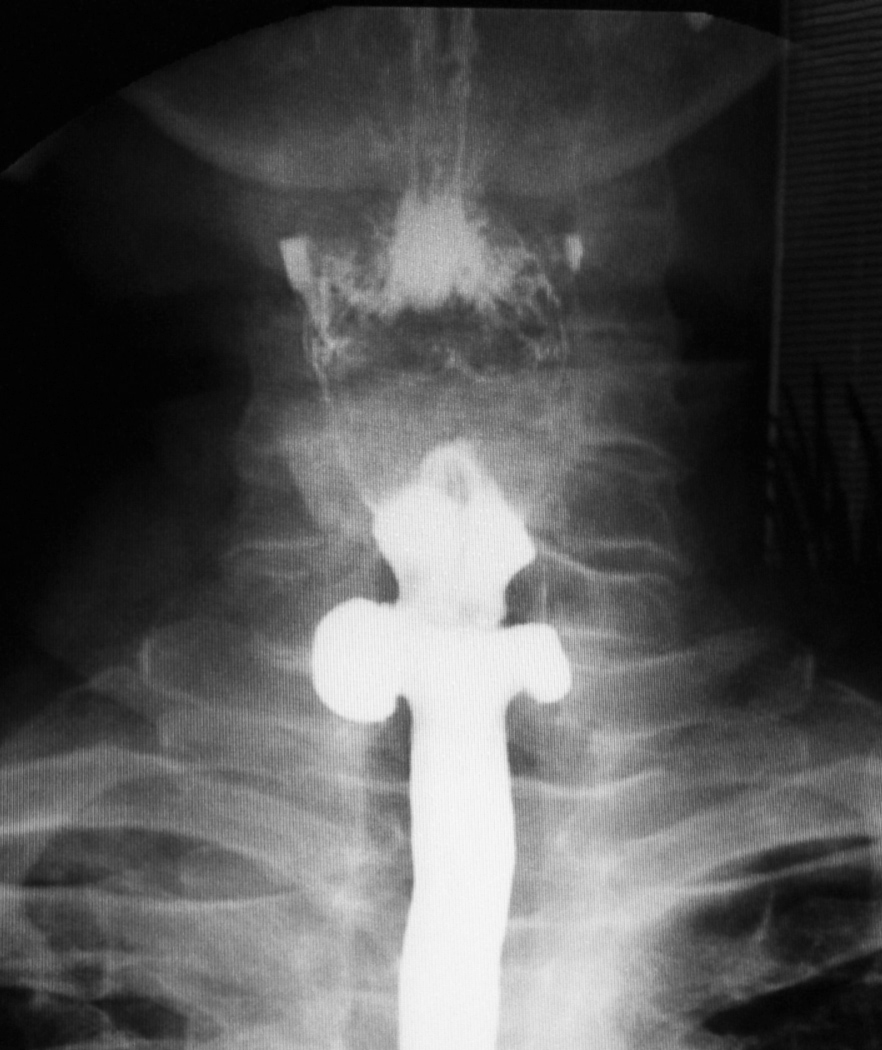

Barium enema showing wide mouth opening of the diverticulum (white …

High-density barium enema with multiple diverticula. The high-density …

Barium enema contrast study showing scattered small diverticula in the …